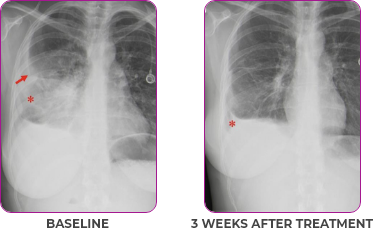

Response in primary and metastatic lesions1

Lung imaging of primary tumors.

SCAN 1: LUNG

SCAN 2: LUNG AND BONE

Images courtesy of Dr Maximilian Hochmair.

Response to VITRAKVI1

- Partial response and symptom improvement confirmed by chest X-rays after <1 month of treatment

- Imaging performed 6 weeks into treatment revealed considerable decrease in the size of both target lesions

- Complete clinical response achieved by 12 months with residual scarring